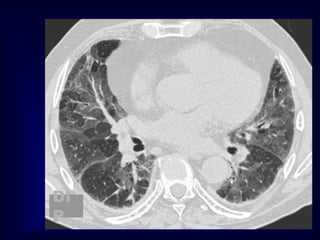

F 78Y Diabetic and hypertensive presented with severe dyspnea

suspected to pulmonary embolism , treated with anticoagulants with mild

improvement